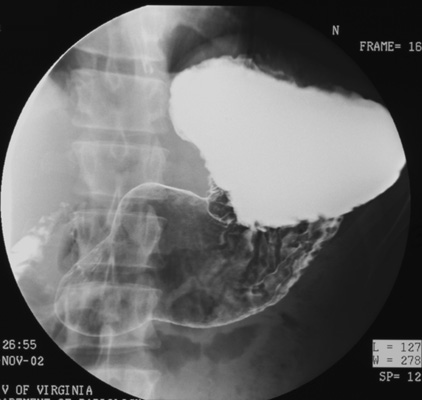

- Gastric antrum (patient LPO)

- Gastric body, inferior portion (patient supine, AP)

- Fundus (patient right lateral)

- Gastric body, superior portion (patient RPO). (Elevate

head of table 15 degrees to keep barium from flowing back into gastric fundus as

he rolls back into RPO position.)